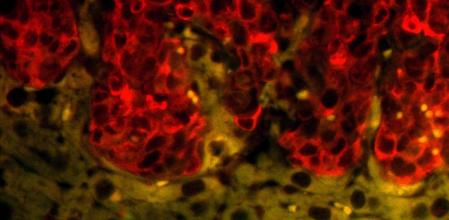

Deteniendo a la proteína HAKAI podría bloquearse la progresión del cáncer

La proteína a la que Figueroa y su equipo pretenden bloquear se llama ‘HAKAI', o destrucción en japonés. Fue identificada y bautizada en 2002 por el Dr. Fujita, que en 2003 se convertiría en el jefe de Figueroa en Londres. HAKAI pertenece a una familia de proteínas destructivas que degrada proteínas indispensables para la fisiología y buen funcionamiento de las células sanas. “El proceso de destrucción de proteínas fue un hallazgo que le valió el Nobel de Química de 2004 a sus descubridores, puesto que se abría un abanico enorme de posibilidades para desarrollar fármacos contra enfermedades como el cáncer”, explica Figueroa.

En 2013, el equipo de Figueroa diseñó las primeras moléculas que hoy son candidatas a atacar a HAKAI evitando la progresión y metástasis del cáncer de colon. En 2019, mejoró las propiedades de estas candidatas, pero para que su trabajo llegue a las unidades de oncología de los hospitales y a sus pacientes, todavía hay que optimizar las propiedades de estos compuestos, con el fin de conseguir un candidato que pueda pasar a una fase regulatoria y ensayos clínicos, algo que puede llevar unos 10 años.